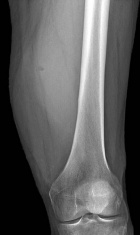

62 year old male with left thigh swelling, soft tissue mass x several years.

Complains of size of the mass, but does not have pain in left thigh.+

Zoom image: Radiological image Radiological image.